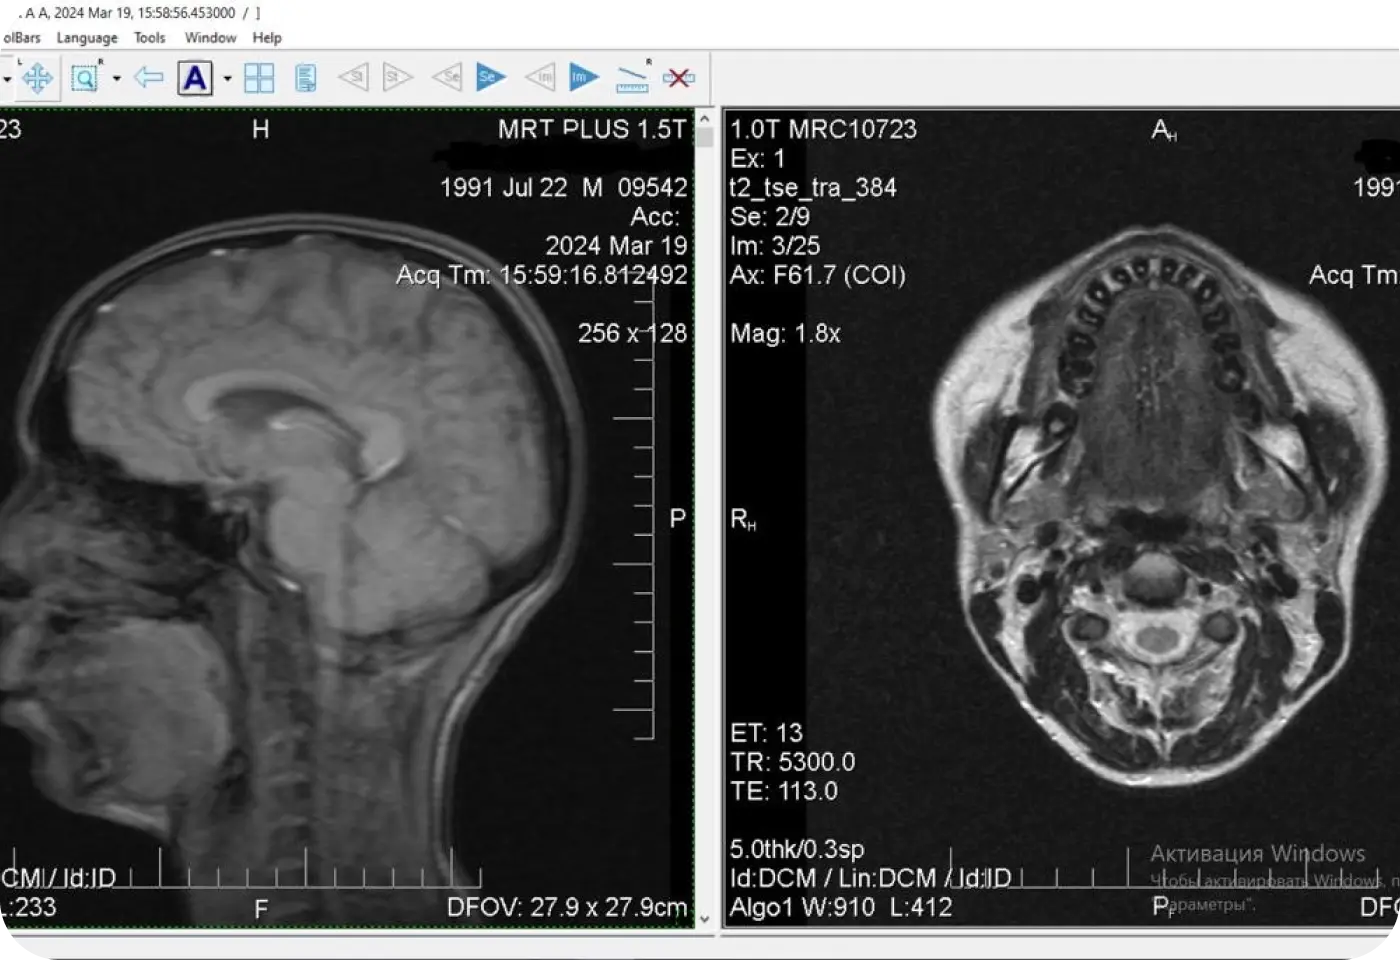

Перед началом лечения я провожу часовую первичную консультацию. Для этой встречи вам необходимо сделать «МРТ ВНЧС» и «КЛКТ двух челюстей с захватом ВНЧС в привычном прикусе».

Во время консультации мы смотрим и анализируем ваши исследования. Я подробно объясняю строение ВНЧС, показываю все причинные факторы вашей проблемы, отвечаю на все вопросы «Почему?»